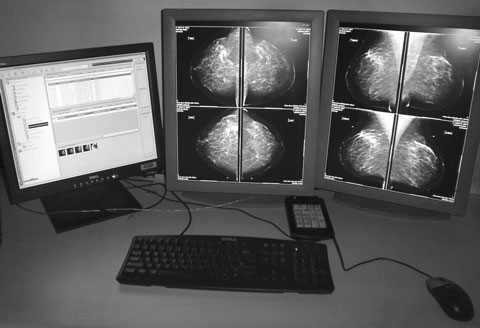

In DM, the steps of image acquisition, display and storage are separated, allowing optimisation of every step.15 DM images are acquired in the same way as CM, but a digital detector replaces the x-ray film cassette. Unlike CM, DM allows manipulation of the stored image. The reader can adjust contrast and intensity, and magnify and move the image, all without acquiring further views (Box 4). Since a digital mammogram is a data file, it can be copied, sent via a network, burned to CD or printed on a mammographic-quality x-ray laser printer. Multiple copies can be reviewed simultaneously at different sites. The capacity for the technologist to immediately view the acquired images for quality assurance and to transmit the data files to a central reading site could make DM an excellent choice for mobile BreastScreen units operating in rural and remote areas.